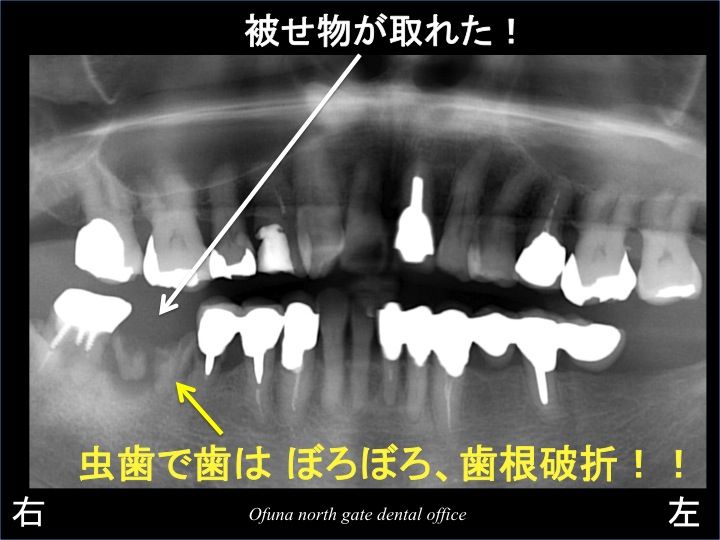

また、暫く患者様の通院が途絶えました。

数ヶ月して突然来院されました。

「被せ物が取れた!」

とのことでした。

取れた被せ物を見てみると ビックリです。

インプラント治療後(取れた物を再度被せ物を付けた後)とは違っていました。

なんと他の歯科医院で 取れた3歯を抜歯しないで新しくセラミックで治療がされていたのです。

そのセラミックを行った歯が取れたというのです。

当たり前です。

抜歯しか治療法がないような状態の歯を 無理矢理セラミックで治療しているからです。

また、取れないように3歯分を連結してありました。

しかし、3歯分を連結した被せ物は、完成から数ヶ月も保たずに再度取れてしまったのです。

ちなみに このセラミックの費用は40万円以上したそうです。